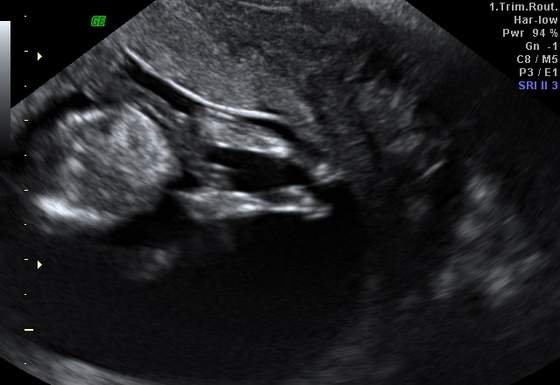

:-) zarabiaste zdjecie masakra :-)

Będzie "w czepku urodzone"! Wiesz, że to wielka rzadkośc i przynosi szczęście dziecku?hehe zrobiłam zdjęcie zdjęcia :-)